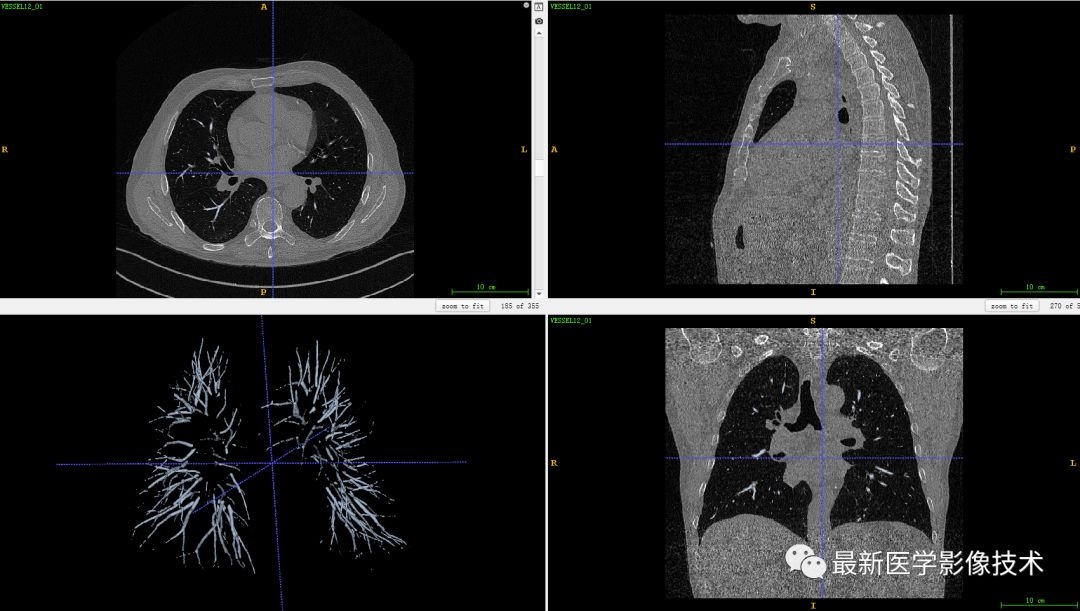

今天分享了人体肺部血管分割并生成三维模型的案例。使用的数据来自VESSEL12挑战赛的公开数据集《VESsel SEgmentation in the Lung 2012》,该挑战赛的任务是从肺部CT图像中使用自动或半自动方法分割出肺部血管区域图像。为了得到肺部整体区域,在这一步骤中可以跳过对血管区域的处理操作。

为了提高图像质量并增强血管区域的可见性,采用Hessian矩阵技术进行增强处理。增强后的血管区域图像显示为明亮的结构,并通过阈值分割方法提取出特征明显的血管区域图像。

最终将该区域与原始CT图像结合,生成了完整的肺部血管三维模型结果。

在之前的讨论中提到过一种有效的方法是利用Hessian矩阵对血管区域进行增强,在医学图像处理案例(六)——生成血管三维模型中对此进行了详细阐述。其中,我们采用的是一个由多维变量函数的一系列二阶偏导数组成的方阵来进行操作,并通过分析其特征值分布特性来进行管状结构检测。经过这一过程后,在增强后的血管区域图像中可以看出明显的增强效果

最后,我们将该区域与原始图像进行结合,生成肺部血管三维模型结果。